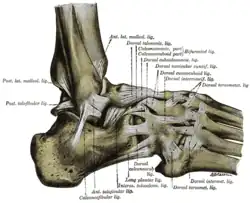

Bänder des Sprunggelenkes

Das Sprunggelenk wird durch eine Reihe von Bändern zusammengehalten. Das Deltaband (Ligamentum deltoideum oder Ligamentum collaterale mediale) besteht aus einem Schienbein-Kahnbein-Teil (Pars tibionavicularis), einem Schienbein-Fersenbein-Teil (Pars tibiocalcanea) und einem vorderen und hinteren Schienbein-Sprungbein-Teil (Pars tibiotalaris anterior und posterior). Das Außenband (Ligamentum collaterale laterale) wird vom vorderen und hinteren Sprungbein-Wadenbein-Band (Ligamentum talofibulare anterius und Ligamentum talofibulare posterius) sowie einem Fersenbein-Wadenbein-Band (Ligamentum calcaneofibulare) gebildet. Die Sprunggelenksgabel wird durch das vordere und hintere Schienbein-Wadenbein-Band (Ligamentum tibiofibulare anterius und Ligamentum tibiofibulare posterius) zusammengehalten. Zwischen dem Hals des Sprungbeins und der dorsalen Oberfläche des Kahnbeins liegt das Ligamentum talonaviculare.